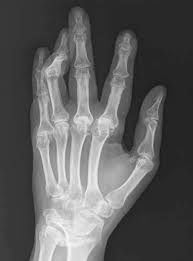

류마티스관절염은 병이 진행될수록 관절과 관절 주위조직의 손상을 유발하고, 결국에는 관절의 변형과 운동장애를 초래한다고 한다.

이미 손상된 관절은 이전 상태로 되돌리기 힘들고 손가락 관절에 장애가 생기면 일상생활을 하는데 지장이 커서 초기에 발견해 치료를 하는 것이 매우 중요하다고 한다.